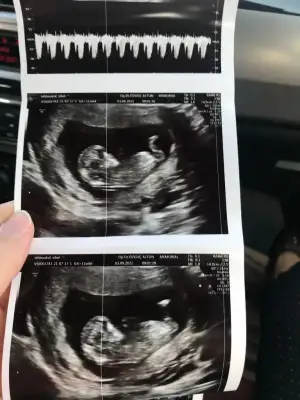

benim icin de tahmin yapabilir misniz 12 haftalik karin usg

Eklentiler

• CD7F8ADF-E6E0-4C01-836E-2E1BE991E8EC.webp

CD7F8ADF-E6E0-4C01-836E-2E1BE991E8EC.webp

44,6 KB · Görüntüleme: 113